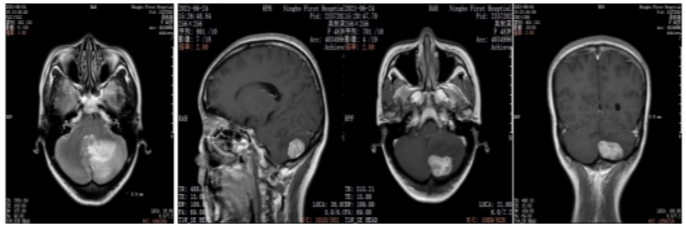

2021年6月颅脑增强MRI:左侧小脑占位,考虑转移瘤。

图2.颅脑增强MRI

2022年5月颅脑增强MRI:左侧小脑肿瘤切除术后改变。

疗效评价CR,继续维持曲妥珠单抗(汉曲优)+吡咯替尼+卡培他滨治疗方案

图3.颅脑增强MRI